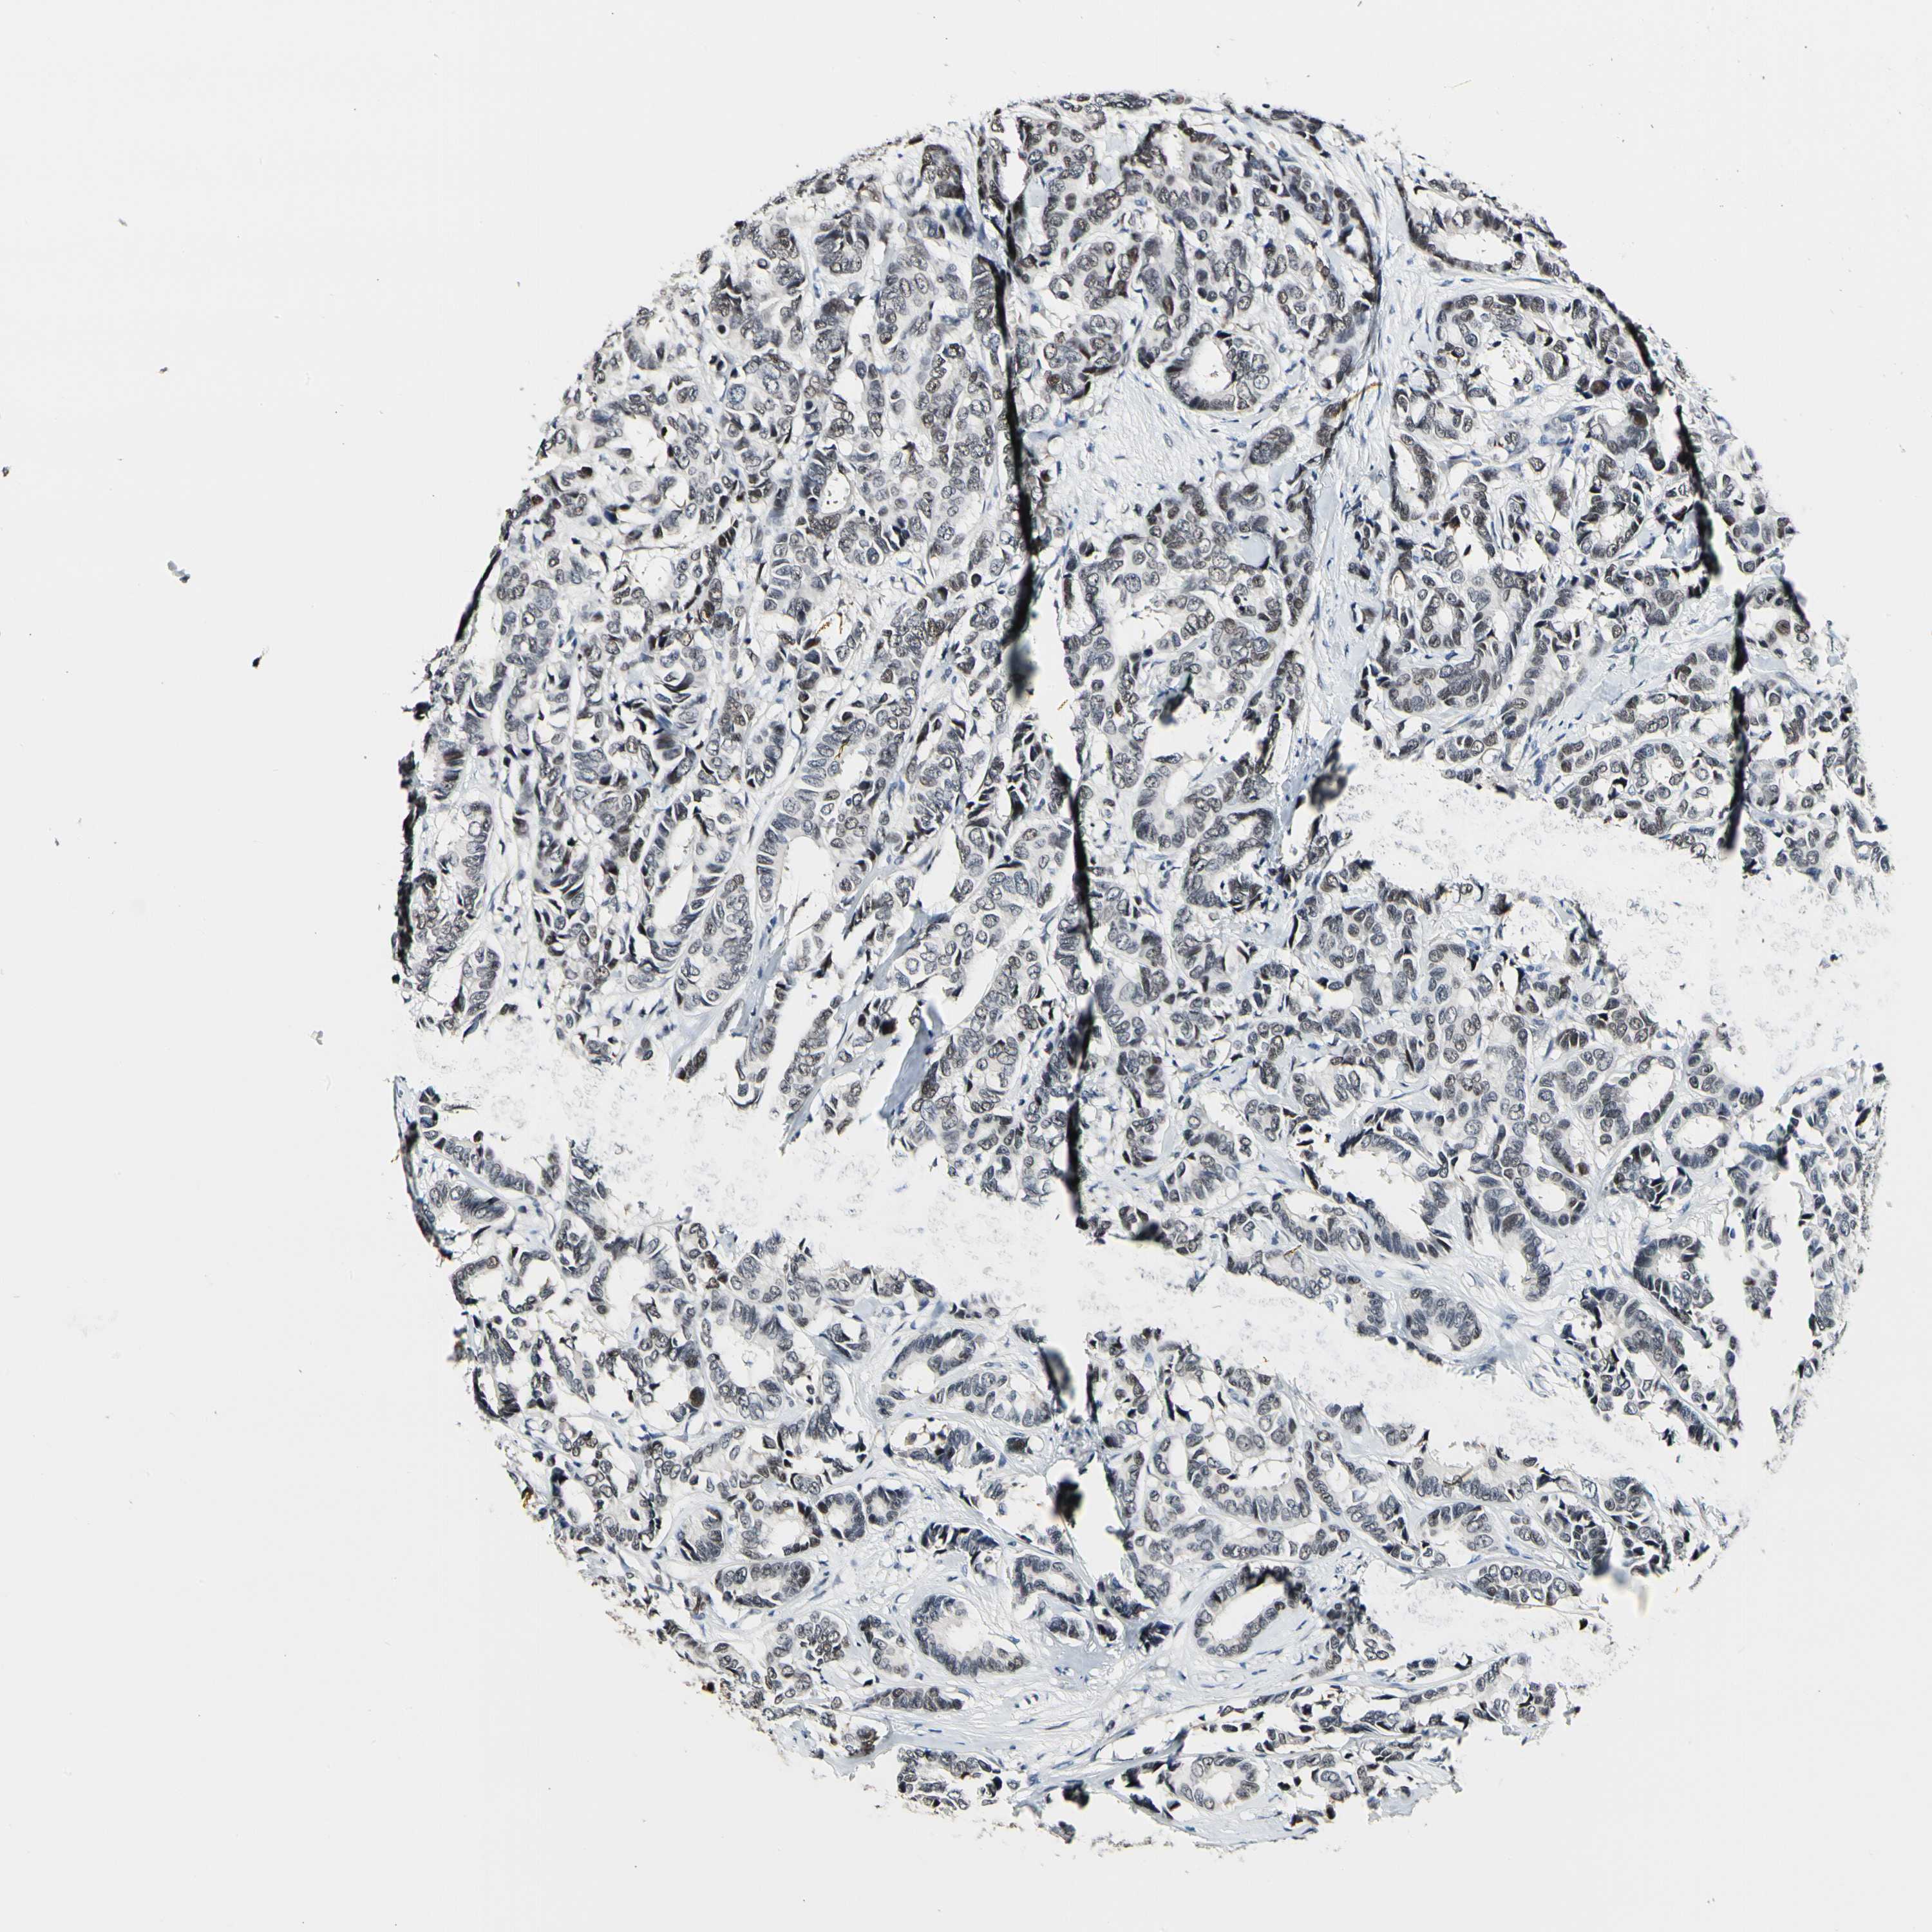

CANCER BREAST CANCER Show tissue menu

BRCA TCGA BRCA VALIDATION PROTEIN EXPRESSION

Breast cancer

Human cancer